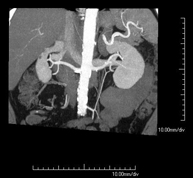

Prueba diagnóstica no invasiva que consiste en el estudio de las arterias renales obteniendo imágenes de alta definición anatómica mediante el empleo de un equipo de TC (Tomografía Computarizada) y de contraste yodado. La calidad de las imágenes permite realizar reconstrucciones en 2D y 3D gracias a estaciones de trabajo especializadas en el estudio arterial. Esta prueba está indicada, por ejemplo, en aquellos pacientes que sufren de HTA refractaria al tratamiento, en pacientes con lesiones renales para tener un mapa "vascular" pre-quirúrgico, etc. - Angio-TC aorto-ilíaco

Prova diagnòstica no invasiva que consisteix en l'estudi de les artèries renals amb l'obtenció d'imatges d'alta definició anatòmica mitjançant l'ús d'un equip de TC (Tomografia Computaritzada) i contrast iodat. La qualitat de les imatges permet realitzar reconstruccions en 2D i 3D gràcies a estacions de treball especialitzades en l'estudi arterial. Aquesta prova està indicat en aquells pacients que pateixen HTA refractària al tractament, en pacients amb lesions renals que tenen un mapa vascular prequirúrgic, etc. - Angio TC d'aorta-ilíaca